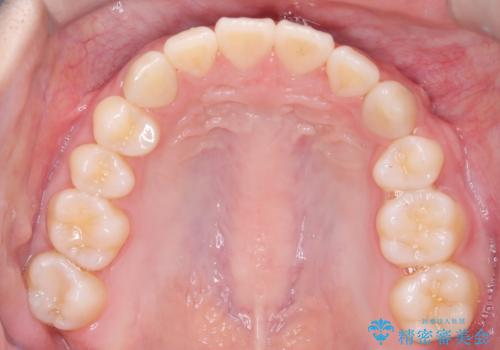

途中、矯正用のアンカースクリューを使うことで、最終的にきれいに前歯の真ん中を合わせることができました。

2年という矯正期間でしたが、かみ合わせも良くなりを患者様には満足していただくことができました。